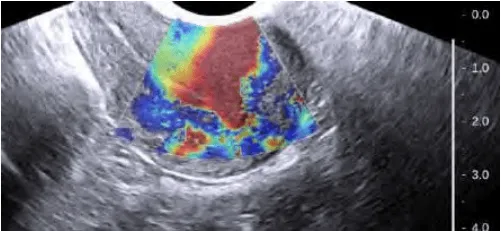

Doppler: Mạch ngoại vi u xơ; Phân biệt với polyp (mạch trung tâm) và adenomyosis (mạch nội vi).

Hình ảnh “U xơ tử cung trên siêu âm Doppler”.

Hình ảnh “Adenomyosis trên siêu âm Doppler”.